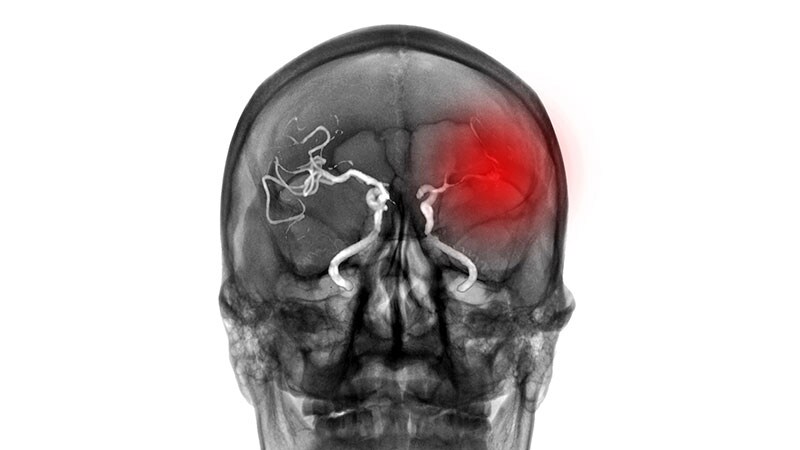

Stroke Thrombectomy Alone Fails Noninferiority to Bridging tPAThe SWIFT DIRECT trial failed to show that direct thrombectomy was noninferior to intravenous thrombolysis plus thrombectomy

for patients with stroke resulting from large-vessel occlusion.